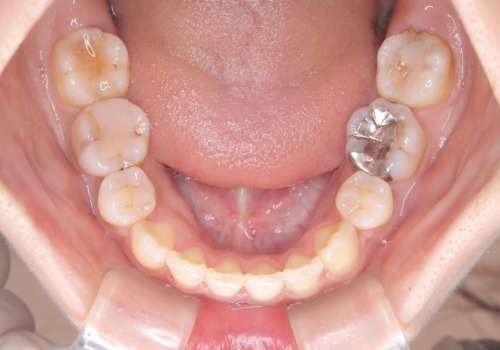

- 主訴:口元を下げて前突感を無くしたい、下の歯の凹凸も無くしたい

右側第二小臼歯、左側第一小臼歯、下顎両側第一小臼歯を抜歯しワイヤ-矯正を行いました。

骨格的顎の変位を認めたため、顔貌に対しピッタリ上下の歯の正中を合わせることは難しいと説明し、上下左右計4本小臼歯を抜歯しワイヤー矯正治療を行いました。